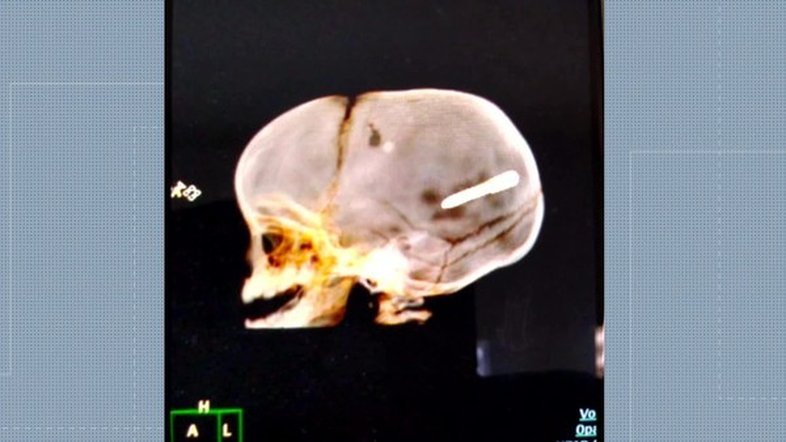

Um bebê de 10 meses, identificado como Wallace Martim dos Santos,  teve a cabeça perfurada com um prego na última terça-feira (30). Ele foi internado em estado grave no Hospital Pedro II no Rio de Janeiro (RJ). As informações são do jornal O Dia.

A família contou que a criança estava no colo da mãe dentro de um carro parado quando o objeto atingiu o veículo. Segundo as primeiras informações, o prego teria partido de uma obra feita na região onde eles estavam.